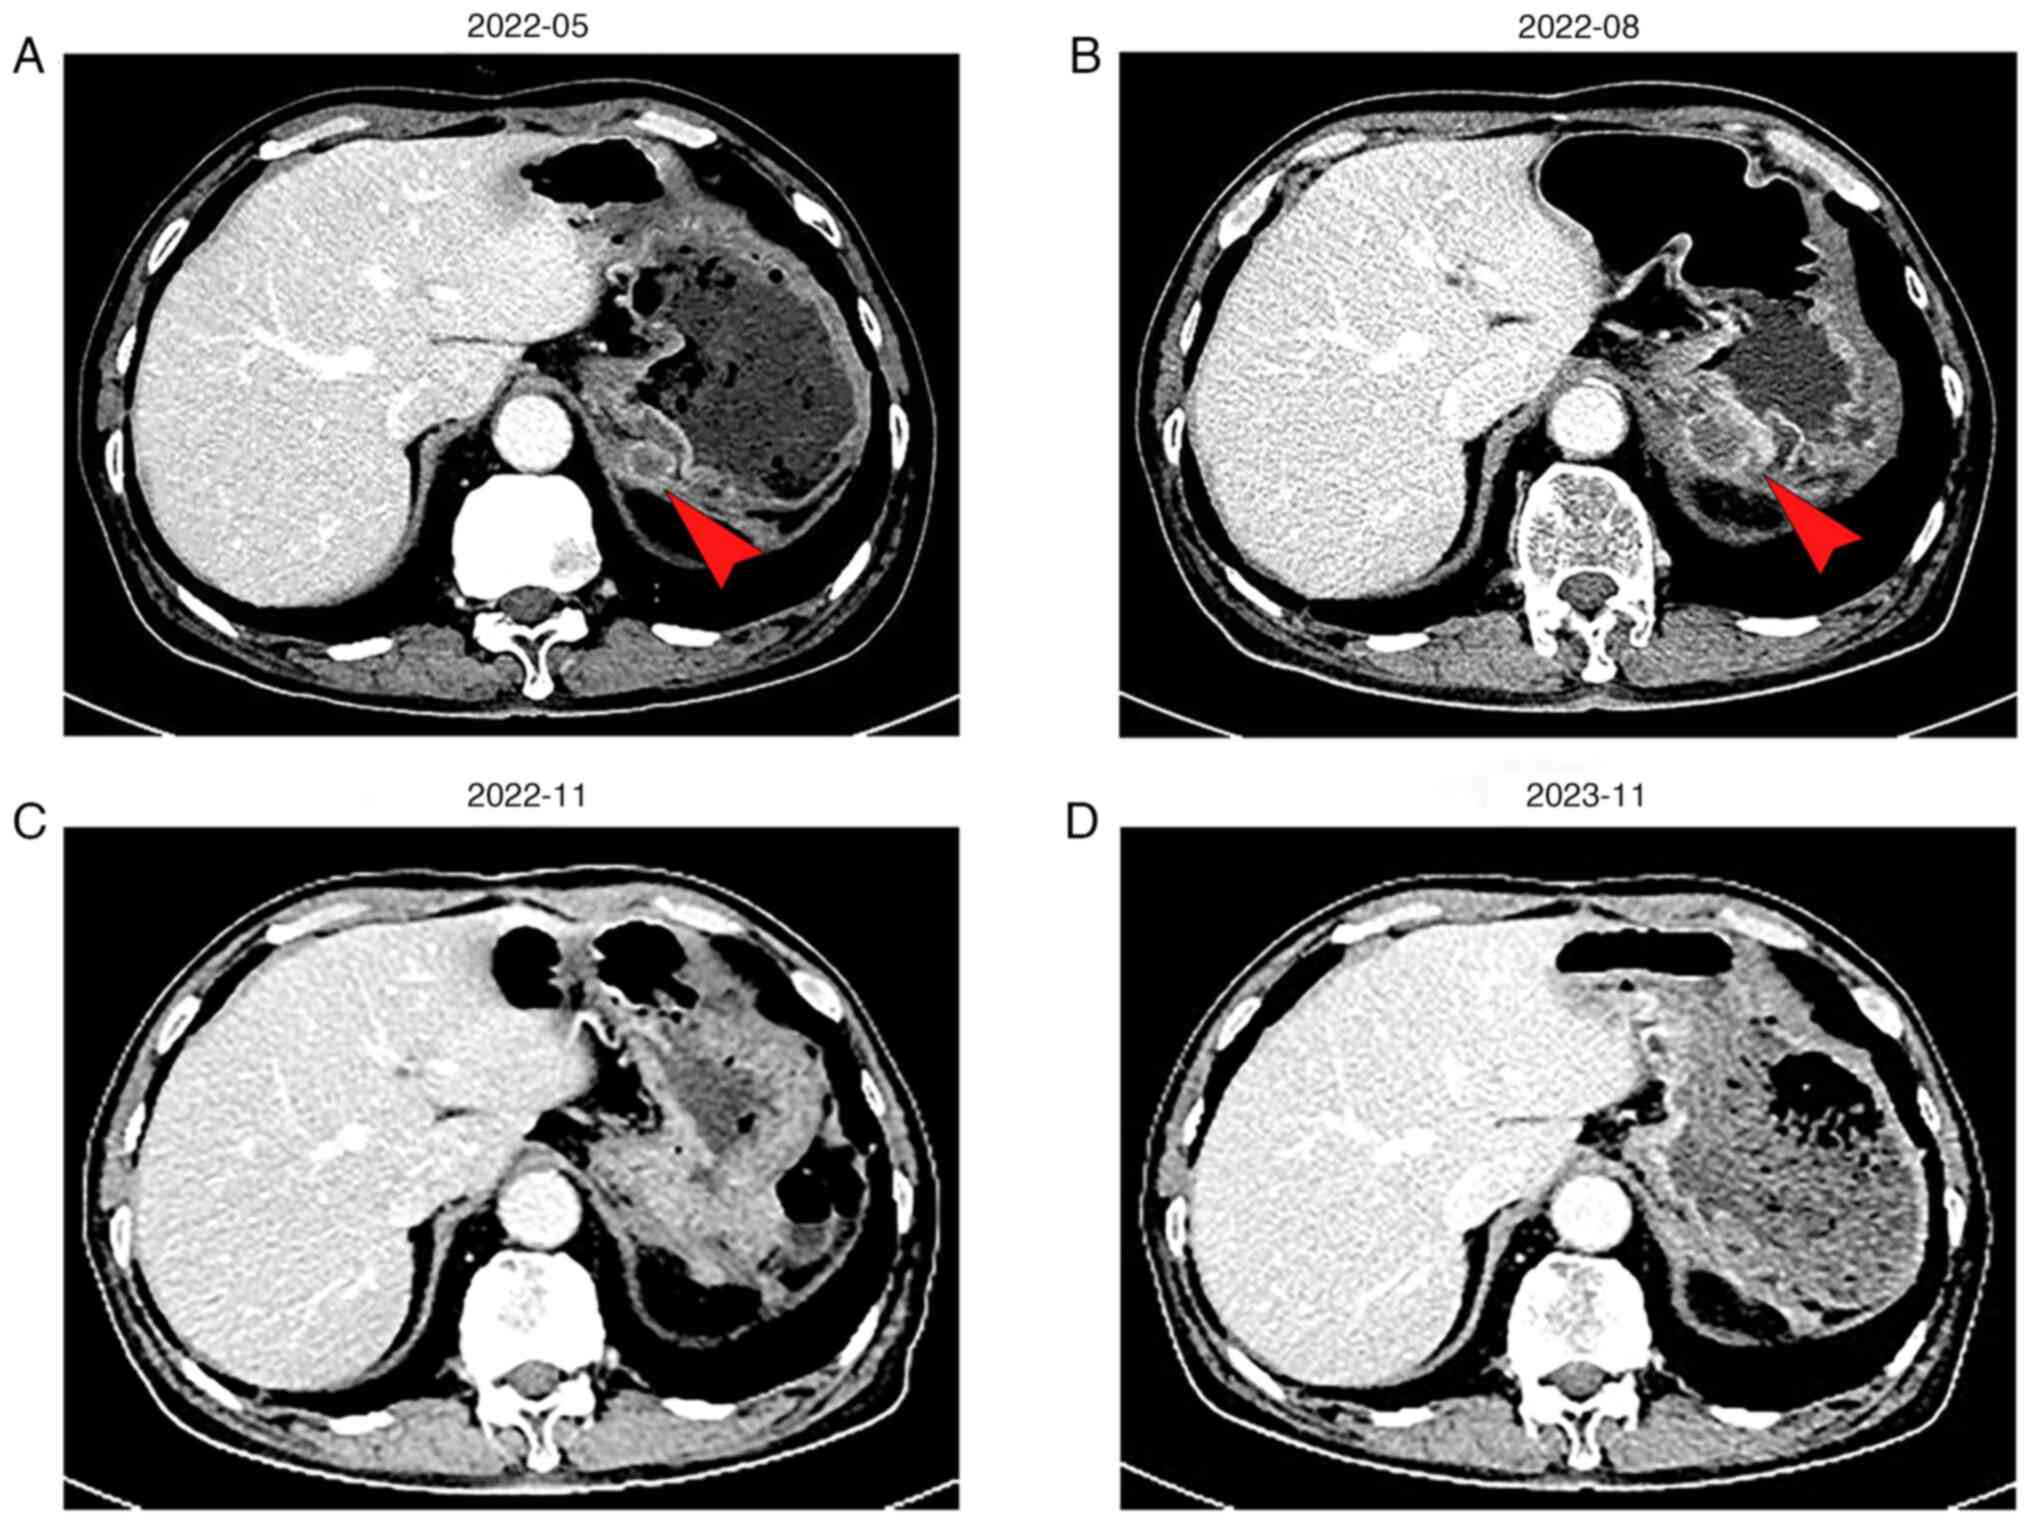

After surgery, the patient declined chemotherapy and other treatments and asked for routine follow-up to monitor the lesion. By May 2022, the patient progressed with the development of a posterior cardiac annular nodule (1.7x1.3 cm) (Fig. 2A) with CA199, which was 35.73 U/ml (Fig. 3). Despite the presence of new lesions, the patient was merely under observation without receiving any treatment. A subsequent upper abdominal CT in August 2022 showed that the nodule had grown to 2.3x2.8 cm (Fig. 2B), and his CA199 level spiked to 124.8 U/ml (Fig. 3). Consequently, the patient was diagnosed with recurrent metastatic PDAC and had an Eastern Cooperative Oncology Group (ECOG) score of 1(19).

Figure 2

CT scan images following recurring metastasis, the red arrow denotes the posterior cardiac lesion location. (A) The initial recurrent CT examination showed a mass behind the cardia, ~1.7x1.3 cm. (B) On follow-up for 3 months, the posterior cardia mass was enlarged compared with the previous one, about 2.3x2.8 cm. (C) After four cycles of combination therapy, the lesion in the posterior cardia had disappeared. (D) After 20 cycles of this combination therapy, no tumor relapse was observed. CT, computed tomography.

In August 2022 the patient was initiated on a treatment regimen comprising of anlotinib (10 mg, days 1-14; 7 days off; 21-day cycle) and tislelizumab (200 mg, day 1; 20 days off; 21-day cycle). Following four cycles of combination therapy, the patient achieved a complete response (CR), with total tumor disappearance (Fig. 2C). To prevent tumor recurrence, the patient continued this regimen without any treatment-related adverse effects. At the latest follow-up in November 2023, the patient remains on this regimen. Abdominal CT scans continue to indicate CR with a progression-free survival (PFS) duration of 14 months (Fig. 2D).